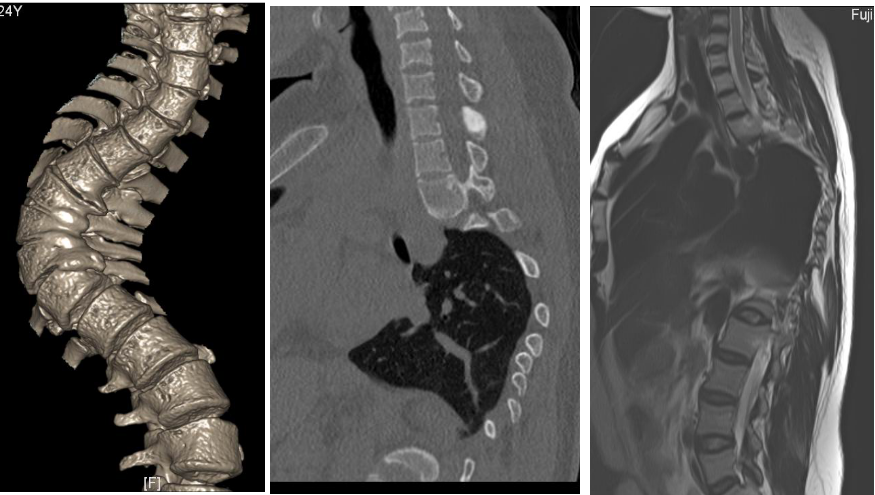

8.jpg

Cobb法:在正位X线相,先确定侧凸的上终椎及下终椎,在主弯上端其上、下终板线向凹侧倾斜度最大者为上终椎,主弯下端者为下终椎。在上终椎椎体上缘及下终椎椎体下缘各划一平线,对此两横线各作一垂直线,这两条垂线的交角即为Cobb角,用量角器可测出其具体度数。